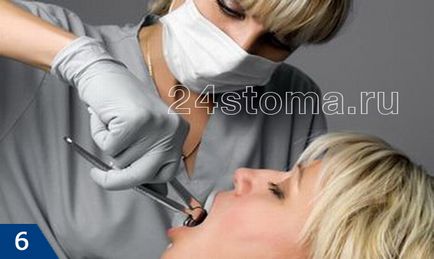

Накладення щипців і розгойдування зуба

щипці накладаються якомога глибше на ту частину зуба, яка знаходиться вище кісткової тканини альвеолярного відростка щелепи. Щільно стиснувши ручки щипців - доктор робить розхитують руху. Це необхідно, щоб зруйнувати зв'язковий апарат, який прикріплює зуб до кістки.